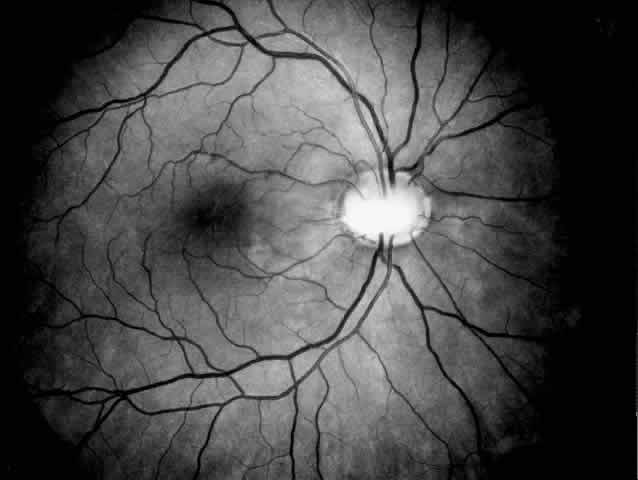

Drusen-like lesions and retinal pigment epithelium damage have also been recognized as a feature of MPGN type II.72–79 In a fluorescein angiographic study of 26 patients who had biopsy-proven MPGN type II, specific fundus lesions were identified in 24 patients (92%).79 Two adolescents with a history of renal disease of 13 months and 2 months had normal fundi. Small-sized lesions similar to small hard drusen were observed in all 24 patients with a history of renal disease lasting for 16 months or more (Fig. 6). In all 15 subjects with a history of renal disease of at least 12 years, larger drusen-like lesions were also noticed. In all 11 patients with renal disease persisting for 18 years or more, drusen occupied most of the fundus and areas of geographic atrophy were seen as well. Foci of new vessels and disciform scarring were observed in eight eyes of five patients with a renal history of 15 years or more (Fig. 7). Most eyes that did not show subretinal neovascularization had normal or nearly normal vision and visual fields. Three patients, however, exhibited ocular symptoms, which were related to pronounced macular atrophic changes, hypertensive retinopathy, and cataracts. The type of fundus lesions was statistically correlated (p<0.0001) with the duration of the renal disease, but not with age, sex, or renal insufficiency. Fundus changes between first and last visit as well as cross-sectional studies suggest a slow progression of retinal disease, which is probably independent of treatment and age of the patient.77–79

Fig. 6. Specific fundus lesions of membranoproliferative glomerulonephritis type II in a 12-year-old child with renal disease since the age of 3 years. The fluorescein angiogram shows numerous small lesions similar to hard drusen. (Leys A, Vanrenterghem Y, Van Damme B et al: Fundus changes in membranoproliferative glomerulonephritis type II: A fluorescein angiographic study of 23 patients. Graefes Arch Clin Exp Ophthalmol 229:406, 1991)

Fig. 7. Fluorescein angiographic changes in a 32-year-old patient with renal signs of membranoproliferative glomerulonephritis type II since the age of 9 years. Numerous small and larger drusen-like lesions, atrophic changes, and a small infrafoveolar subretinal neovascular membrane that was successfully treated with argon laser coagulation can be seen. (Leys A, Michielsen B, Leys M et al: Subretinal neovascular membranes associated with chronic membranoproliferative glomerulonephritis type II. Graefes Arch Clin Exp Ophthalmol 228:499, 1990)